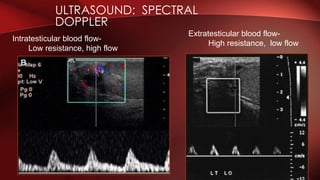

• Spectral Doppler tracings of testicular arterial inflow demonstrate

relatively low resistance

• The cremasteric and deferential arteries which have relatively

high resistance to flow.

• The normal testicular artery resistive indices in adults range from

46% to 78%, with a mean of 64%.

ULTRASOUND: SPECTRAL

DOPPLER

Extratesticular blood flow-

High resistance, low flow

Intratesticular blood flow-

Low resistance, high flow

ULTRASOUND: SPECTRAL DOPPLER Extratesticular bloodflow- High resistance, low flow Intratesticular blood flow- Low resistance, high flow

• #10 Intrastesticular supply- TESTICULAR a off aorta, low resistance with high flow Extratesticular supply- DEFERENTIAL and CREMASTERIC a, high resistance with low flow Flow during diastole